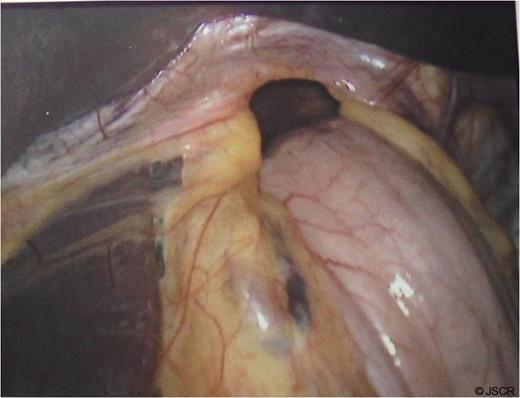

At operation, a large hiatal defect of 5cm and a moderate size sac was found (Fig 1) that was mobilised and adhesions divided to obtain 3cm of oesophageal length in the abdomen. Following division of the upper short gastric vessels, a posterior hiatal repair with seven interrupted ethibond stitches and a loose 360 degree full wrap with the fundus of the stomach with three interrupted ethibond stitches were performed. Wrap was further fixed to the diaphragm and right crus with another three ethibond stitches (Fig. 2).

Hiatus hernia with portion of stomach seen going into the chest